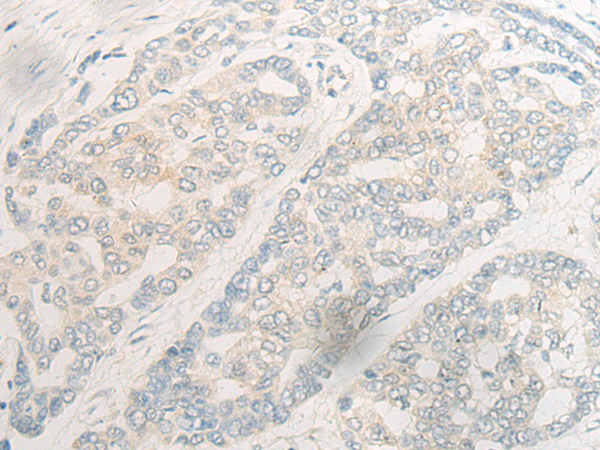

分类: 科研抗体货号: P06367别名: UHX1应用: IHC反应种属: Human